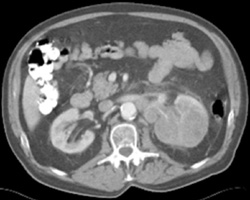

Left Gonadal Vein and Ureteropelvic Junction (UPJ)